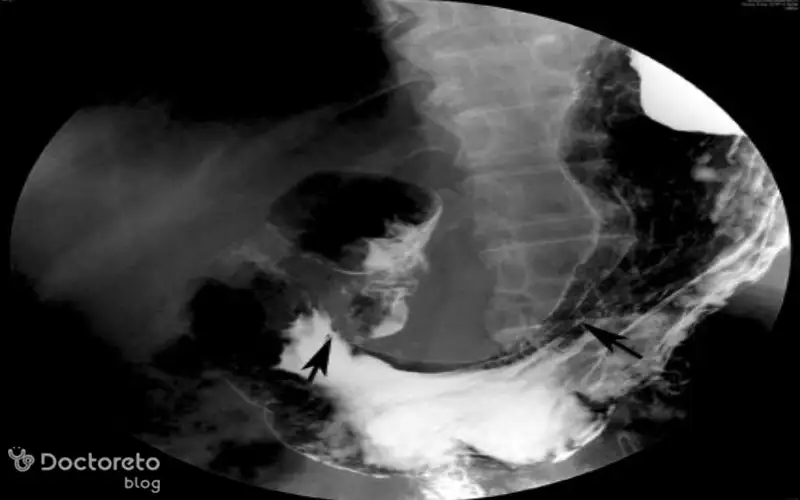

عکس تصویربرداری های سرطان معده خوش خیم

تصویربرداری پزشکی مانند سیتیاسکن و MRI به پزشکان کمک میکنند تا موقعیت، اندازه و ماهیت تومورهای معده را بررسی کنند. در ث تومورهای خوشخیم نیز این روشها کاربرد دارند تا احتمال نفوذ به بافتهای مجاور یا تبدیل احتمالی به بدخیم بیشتر و با دقت بالاتر ارزیابی شود. عکس این بخش نمونهای از این نوع تصویربرداریها را نشان میدهد.

عکس سی تی اسکن سرطان معده خوش خیم

سیتیاسکن ابزار قوی دیگری برای ارزیابی تومورهای معده است. این روش تصویربرداری به ویژه در تشخیص اندازه، موقعیت و ارتباط آنها با ساختارهای اطراف کاربرد دارد. حتی برای سلولهای خوشخیم سرطانی هم سیتیاسکن اطلاعات ارزشمندی در مورد چگونگی رشد و وضعیت بیمار ارائه میدهد. استفاده از این تصاویر کمک میکند تا پزشک نگاهی دقیقتر به تومور معده داشته باشد.